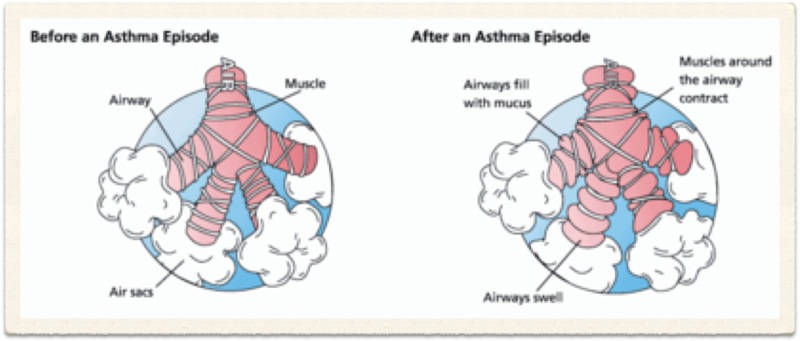

Chronic Obstructive Pulmonary Disease (COPD) is an 'umbrella' term for people with chronic bronchitis, emphysema, or both. With COPD the airflow to the lungs is restricted (obstructed). COPD is usually caused by smoking. Symptoms include cough and breathlessness.